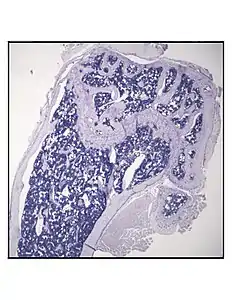

Representative distal femur histologic section of a 16-week-old healthy C57BL/6 mouse demonstrating a typical quantity of marrow adipocytes.